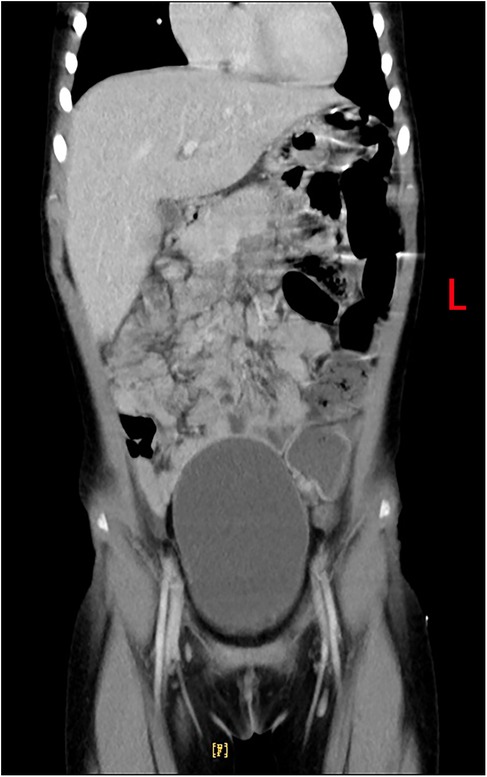

The patient made a full recovery, with no further episodes of fever or abdominal pain, following a 10-day course of oral metronidazole (0.2 g orally, three times daily), in conjunction with continued vancomycin administration for a total of 40 days. Repeated infection markers and bone marrow cultures were negative. Enhanced thoraco-abdominal CT scans showed a significant reduction in the size of the liver abscess (Figures 3A,B), and abdominal ultrasound indicated gradual improvement of liver function prior to discharge. Remarkably, a follow-up CT scan performed 4 months later revealed complete resolution of the liver abscess and normalization of her liver architecture (Figure 4).